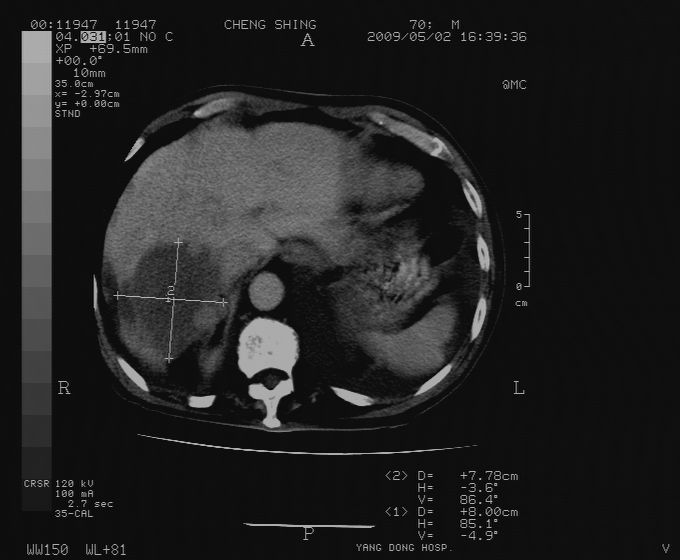

标题: CT19743:男70岁,肺部疾病入院,B超发现肝右叶占位,CT [打印本页]

标题: CT19743:男70岁,肺部疾病入院,B超发现肝右叶占位,CT

肝表面塌陷,病灶周围有子灶,前面较大子灶强化符合肝癌表现,考虑肝癌肝转移可能性大.

1)考虑肝癌并肝内转移。2)少量腹水。3)双侧胸腔积液。

1)考虑肝癌并肝内转移。2)少量腹水及双侧胸腔积液。3)椎体退变。